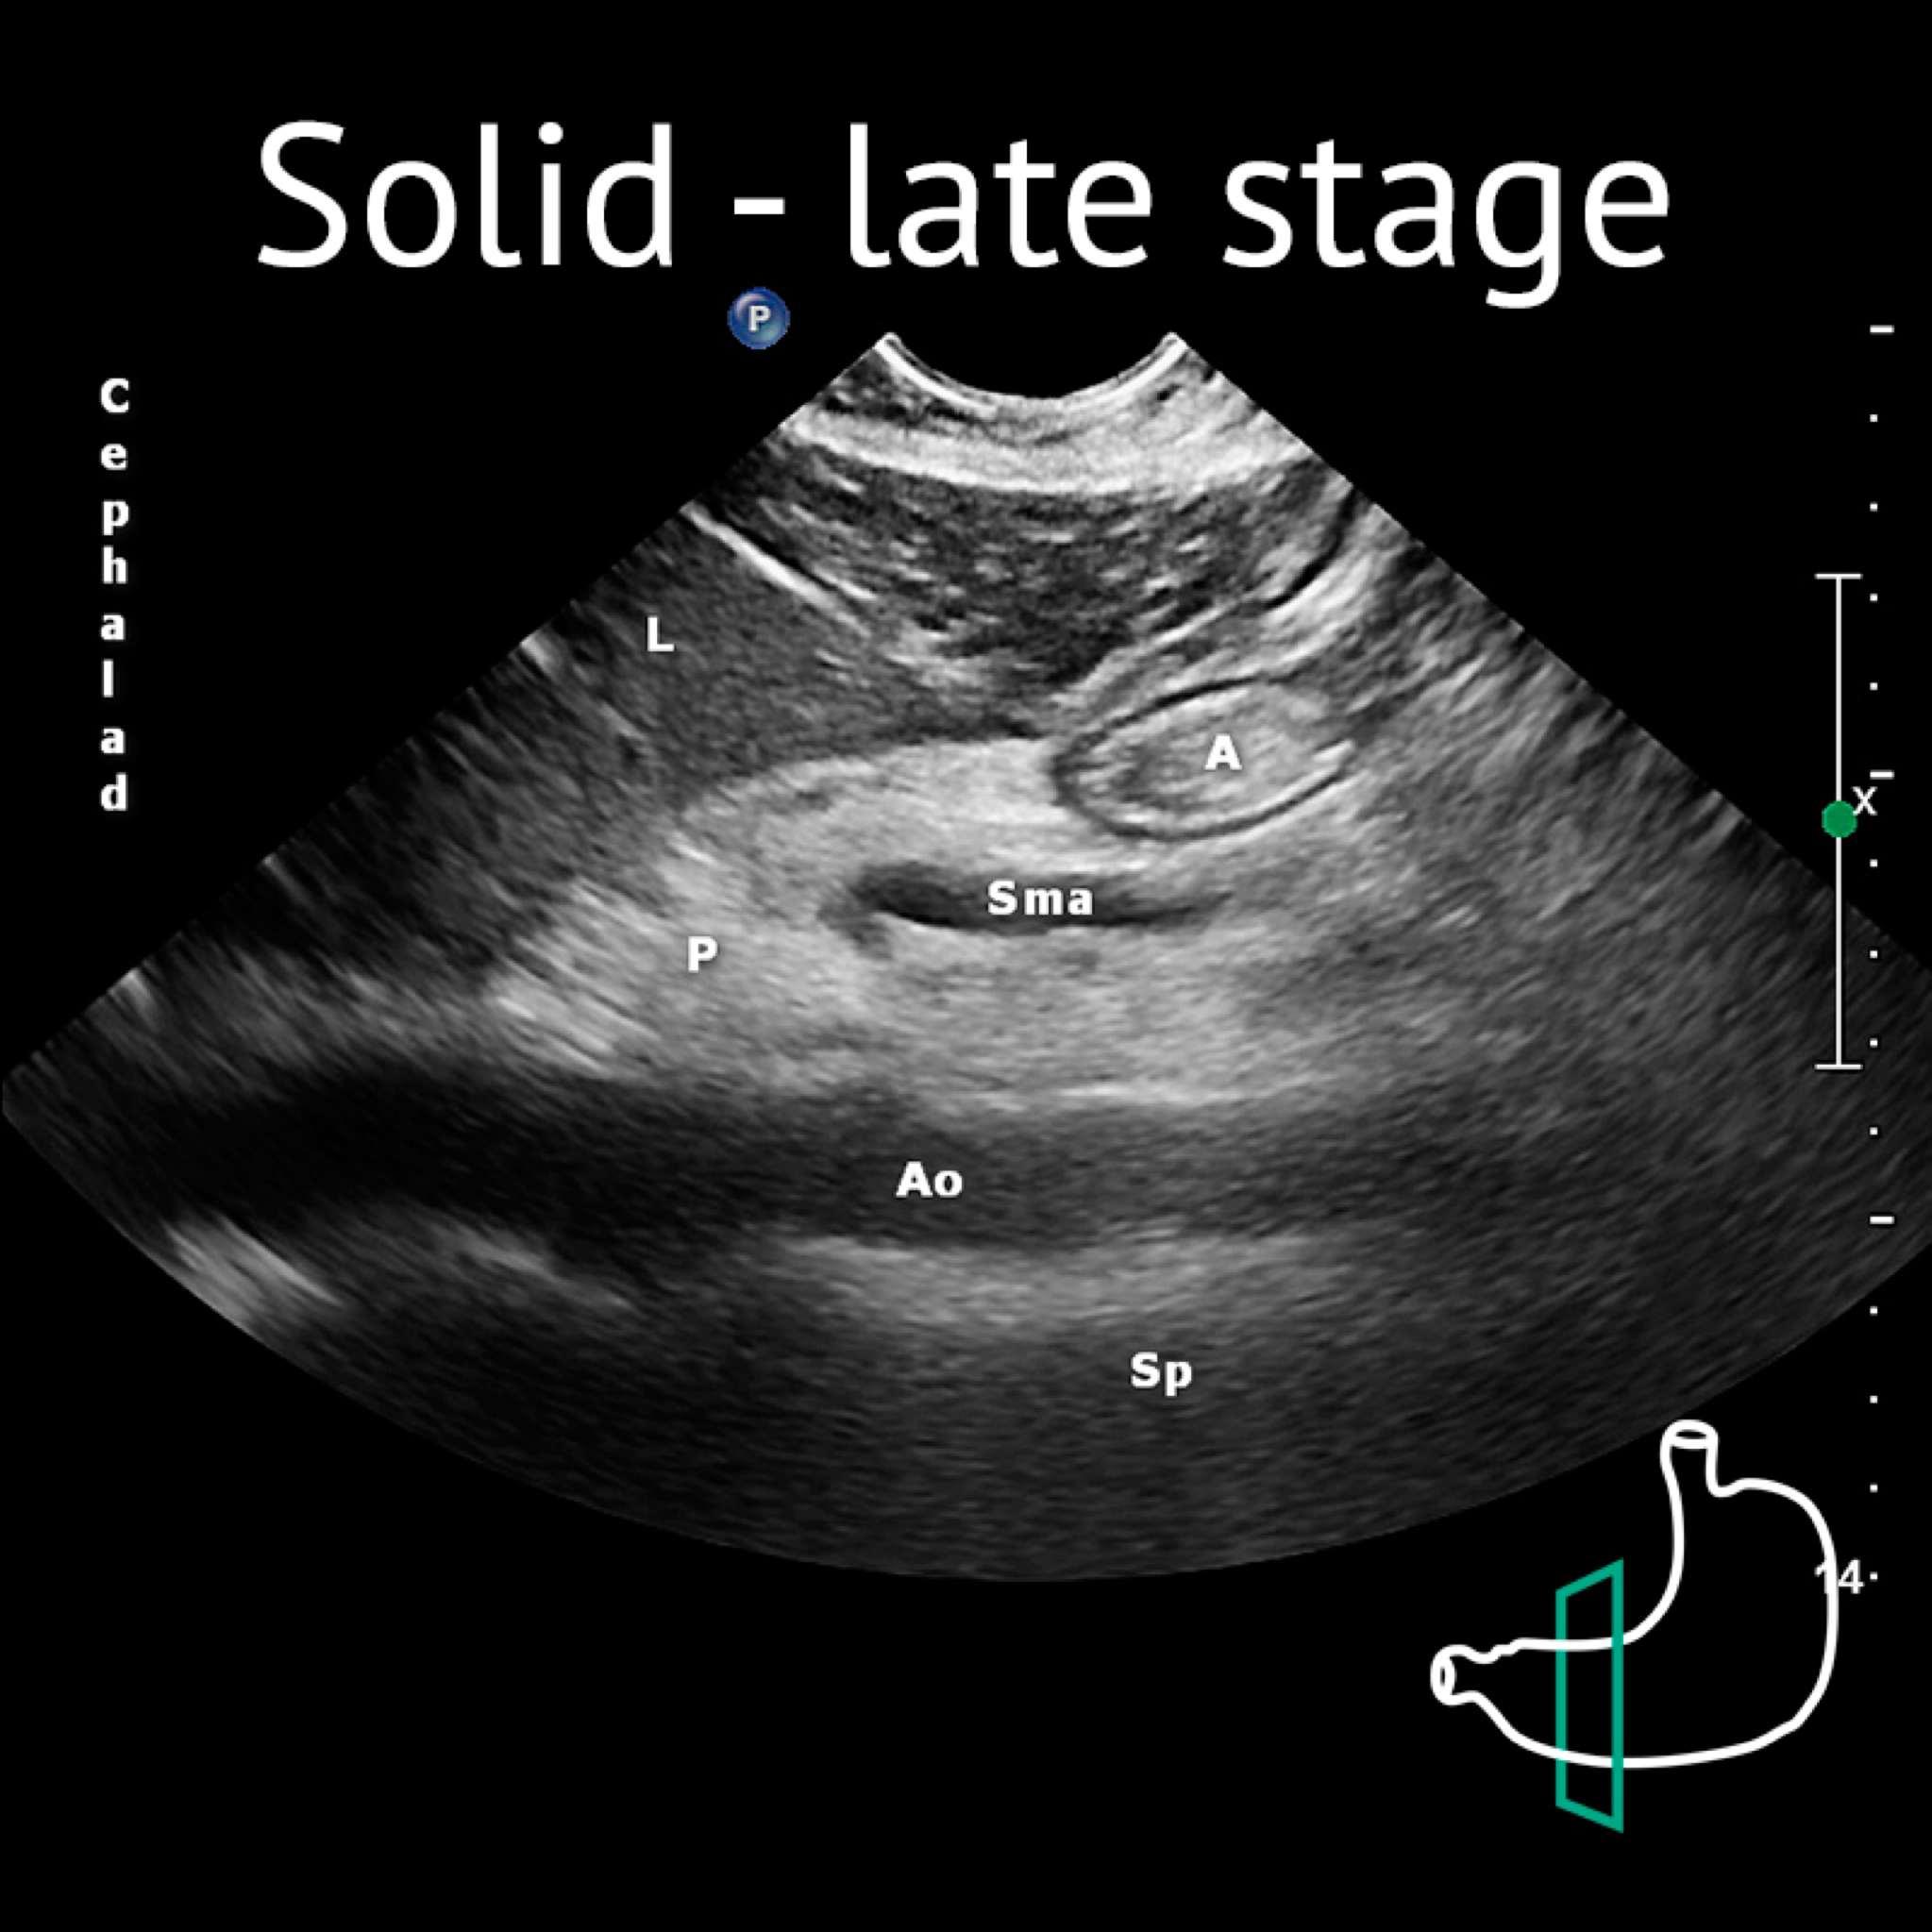

A: antrum; Ao: aorta; L: liver; P: pancreas; Sma: superior mesenteric artery; Sp: spine